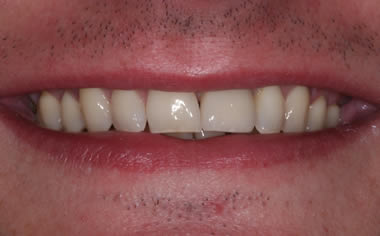

More front teeth replaced by dental implants

Case Three (4 images)